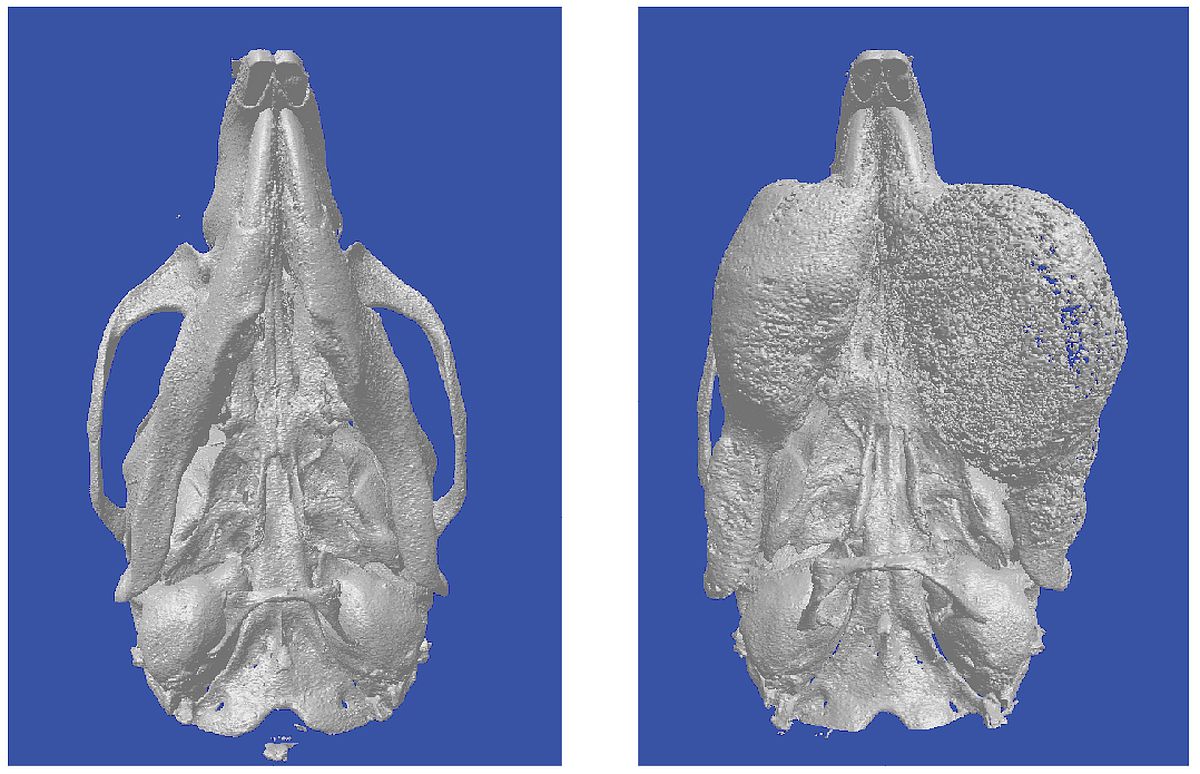

Another side-effect of the seven-year-long research: In some cases, the loss of menin in the osteoclasts of mice led to the formation of a tumour in the lower jaw. Experts of the Bone Tumour Reference Centre in Basel, a cooperation partner of the CME, pointed out the similarity with the ossification syndrome found in humans. This little researched tumour disease leads to heavy cell growth in the lower jaw. At present, this very rare, benign tumour can only be treated with invasive and disfiguring surgeries. Until now, little was known about the triggering factors of this tumour disease. In a mouse model, the researchers in Ulm have now discovered that menin controls the cell growth inhibitor p21 - and thus suppresses the growth of tumours. When menin is absent, p21 reduces its activity and certain cells start to grow increasingly.

In a next step, the CME and the colleagues from the German-Austrian-Swiss Task Force for Tumours of the Jaw and Face (DÖSAK) will analyse human specimen of the ossification syndrome in order to test the findings from the research on mice. 'We are hoping to find therapeutic approaches that can prevent the development of these tumours,' says Tuckermann. Animal experiments cannot always be avoided in this type of work. The researchers do make sure to keep the numbers of animals at a minimum while still being able to draw valid conclusions for the explanation of human disease patterns. The project received funding from the German Research Foundation through the focus programme Immunobone 1468, the Trauma SFB 1149 and the Trilaterale Consortium Tu 220/12-1.